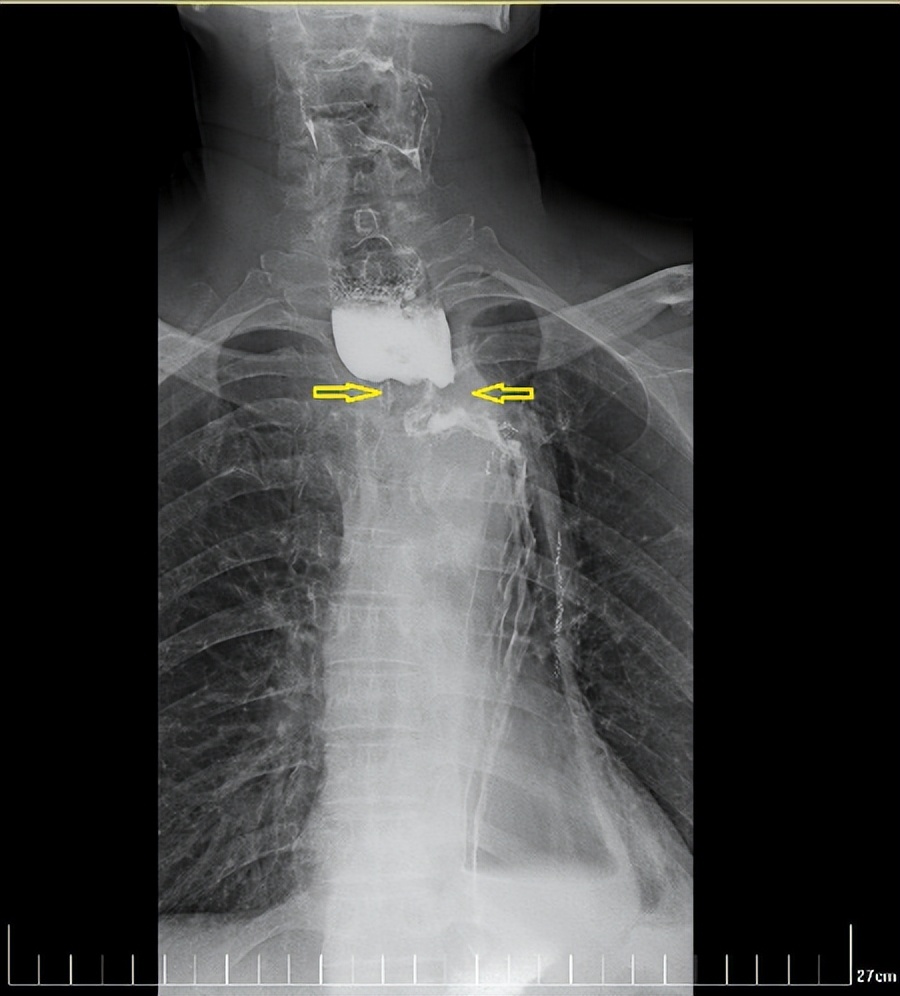

经过一个周期的放疗,李先生明显感受好多了,可以正常吃饭喝水。食管钡餐造影显示,食管吻合口区肿块明显缩小,食管狭窄减轻。

治疗前